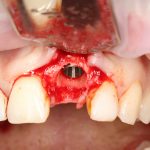

Рекомендации по установке имплантов. Для всех. Часть V.